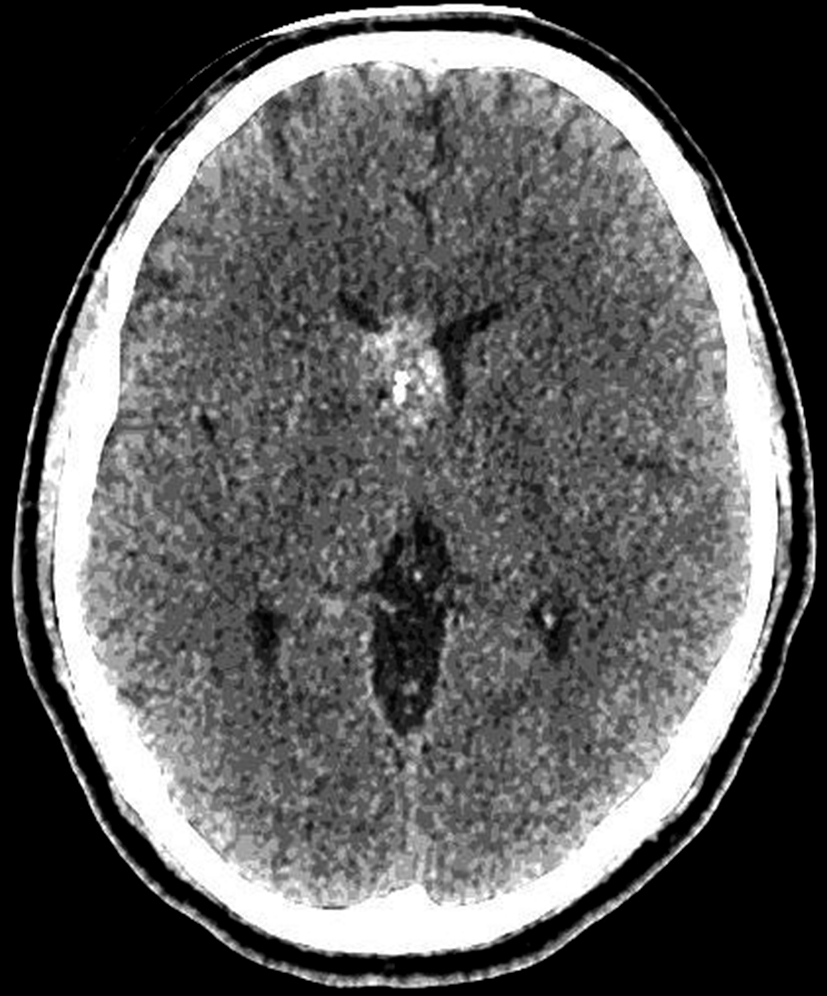

Se presenta el caso clínico de un paciente de sexo masculino, de 36 años de edad, sin antecedentes personales a destacar. Consulta por cefalea holocraneana de larga data, sin déficit neurológico y examen físico normal. Dada la clínica del paciente se realiza una tomografía computada de cráneo sin contraste intravenoso que identifica una lesión bien definida espontáneamente hiperdensa, heterogénea con calcificaciones puntiformes localizada en el asta frontal del ventrículo lateral derecho. No hay edema peri-lesional, efecto de masa ni hidrocefalia (Figura 1- A). Debido a los hallazgos se decide administrar contraste intravenoso, no evidenciándose realce significativo de la lesión (Figura 1- B).

Se efectúa un control imagenológico al año del diagnóstico mediante una TC sin y con contraste (Figura 5 – A y B), donde se evidencia la lesión sin cambios significativos en cuanto a su tamaño y características.

Figura 1

a) TC sin contraste. Lesión

intraventricular hiperdensa,

heterogénea con pequeñas

calcificaciones.

a) TC con contraste. No se

identifica realce significativo

de la lesión.

Figura 5

a y b) Cortes axiales de TC sin y con contraste intravenoso. Control

tomográfico al año

del estudio inicial, no

se observan cambios

significativos de la lesión.